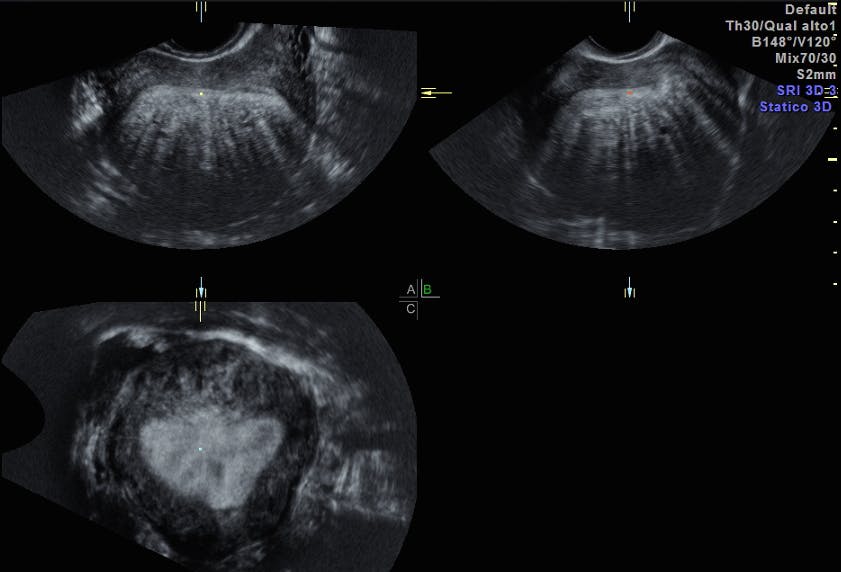

Why Adenomyosis Ultrasound Could Replace MRI in Diagnosis Empowered Fan Shaped Shadowing a systematic evaluation of myometrial mass includes evaluation of outline, echo structure, and vascularity. fan‐shaped shadowing should be present behind the myometrial lesion. As a rule of thumb, finding edge shadows. Fan Shaped Shadowing.

Sonographic findings in adenomyosis [30]. (a) Spherical, (b) wall Fan Shaped Shadowing As a rule of thumb, finding edge shadows. fan‐shaped shadowing should be present behind the myometrial lesion. a systematic evaluation of myometrial mass includes evaluation of outline, echo structure, and vascularity. Fan Shaped Shadowing.